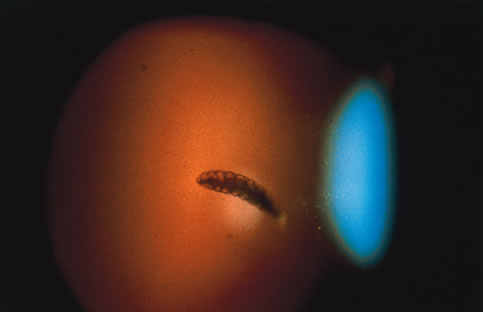

In primary ocular HSV infections, a severe follicular conjunctivitis with regional adenopathy is present. Vesicles may appear on the eyelid skin or lid margin, producing blepharitis (Fig. 3). Corneal involvement initially takes the form of a superficial punctate keratitis, which may progress to dendritic or geographic ulceration. Stromal infiltrates and uveitis are less common and relatively mild in primary disease. In uncomplicated cases, lesions usually heal completely in 2 to 3 weeks without scarring. Most cases of ocular HSV are recurrences. Recrudescent ocular herpes may take the form of dendritic or geographic ulcers, recurrent erosions, interstitial or disciform stromal keratitis, and anterior uveitis.3 HSV may also be an agent of retinitis and acute retinal necrosis (Fig. 4).

Involvement by VZV of the first division of the trigeminal nerve is referred to as herpes zoster ophthalmicus regardless of whether the eye is inflamed (Fig. 5). Eighty-five percent of patients with cutaneous eruptions on the side of the tip or midportion of the nose (Hutchinson's sign) will have ocular involvement. Varicella zoster virus can cause blepharitis, canaliculitis, episcleritis, scleritis, conjunctivitis, keratitis, iridocyclitis, uveitis, retinal vasculitis, retinitis, choroiditis, and optic neuritis. Cataracts and glaucoma are late complications related to the uveitis and long-term use of topical corticosteroid therapy.

Corneal complications occur in the majority of patients with herpes zoster ophthalmicus. A punctate epithelial keratopathy with pseudodendrite formation is the earliest and most common lesion that occurs. Stromal infiltrates, disciform reactions, and rarely interstitial keratitis are also observed. Scarring and contracture of the lid margin often results in trichiasis, distichiasis, entropion, or ectropion. Corneal sensation is reduced, and neurotrophic ulceration, corneal melting, or perforation may ensue. Extraocular muscle involvement with facial paresis has been observed.11